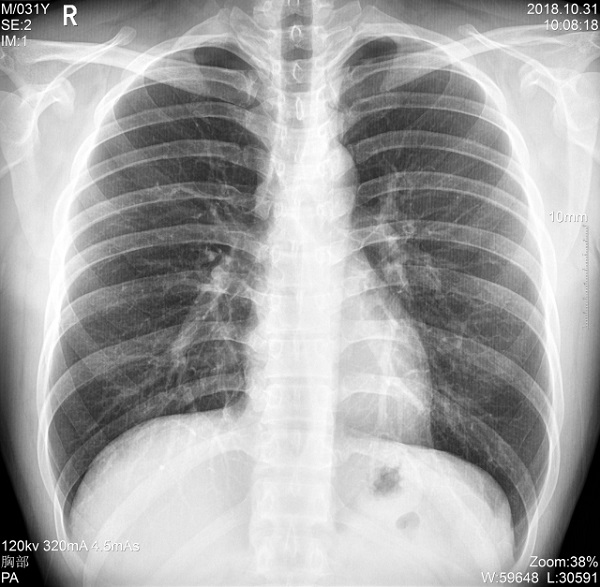

常规固定式X光机:功率中等,通常在10-50kW之间,用于普通放射科检查(如胸部、骨骼X光)。

如普爱PLX5500医疗X光机,设备定位是一款大功率的移动DR,其搭载了最大65kW功率的球管,输出的射线能够满足各体型患者的拍摄需求,更配有最高300kHU阳极热容+1250kHU管套热容,能够满足大规模体检、肺炎筛查等连续拍摄的需求。